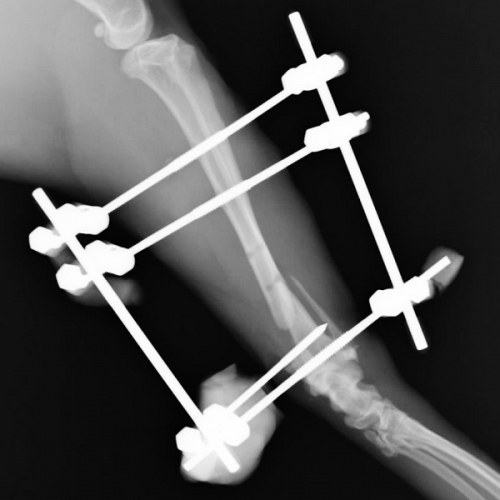

下の写真は骨折の整復手術の開始から2時間超、骨折端の位置決めが終わって、手術もそろそろ佳境に差し掛かった時点での写真です。

レントゲン写真は、レジンでの補強後の最終的なものです。骨折直後の写真と比べてると、大きくずれていた骨折部位がほぼ戻っているのがおわかりになるでしょうか?

下は手術後の側面からのレントゲン写真です。しっかり固定できましたので、この後は骨の癒合を待つだけです。運動制限はありますが、創外固定の器具が健康な骨の代役を担ってくれますから、猫ちゃんは手術後には自由に動き回ることができます。